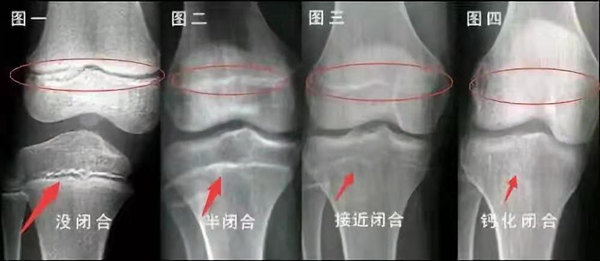

我們都知道,人體的高矮是由骨骼的生長(zhǎng)發(fā)育決定的,特別是下肢長(zhǎng)骨。長(zhǎng)骨呈長(zhǎng)管狀,在長(zhǎng)骨的兩端有一種專(zhuān)管骨骼生長(zhǎng)的骺軟骨,它與干骺端之間有一盤(pán)狀軟骨結(jié)構(gòu)稱為骺板(線),在幼兒的X光片上表現(xiàn)為一條較寬的透光帶。 (見(jiàn)下圖)

未成年時(shí)隨著年齡的增加骺軟骨端不斷骨化,骨骼就不斷增長(zhǎng)。當(dāng)骨骺線完全閉合時(shí)骨骼就停止生長(zhǎng),個(gè)子也就不再增長(zhǎng)了。一般骨骺端完全閉合的年齡是18~20歲左右。